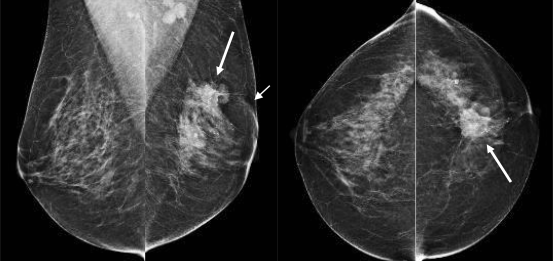

BI-RADS-classificatie 4: verdacht

Afwijkingen met deze classificatie hebben niet het klassieke aspect van een maligniteit, maar zijn wel voldoende verdacht om te biopteren (fig. 9). Als aan een afwijking de eindclassificatie BI-RADS 4 wordt gegeven, kan het zijn dat de afwijking toch benigne blijkt.

De kans op maligniteit varieert in deze categorie sterk van 2–95 %, daarom kan optioneel gebruikgemaakt worden van subclassificaties, 4a, 4b en 4c, zodat de patiënt en de verwijzer beter geïnformeerd worden over de kans op maligniteit; zie hiervoor tab. 1.

Figuur 9

Onscherp begrensde irregulaire massa laterale onderkwadrant linkermamma (pijlen). Door de vorm en de begrenzing is de massa verdacht voor maligniteit, maar door de horizontale ligging is er evenveel kans dat het een veldje klierweefsel betreft, bijvoorbeeld met atypie. BI-RADS 4b, matige verdenking op maligniteit (pathologie: infiltrerend ductaal carcinoom).